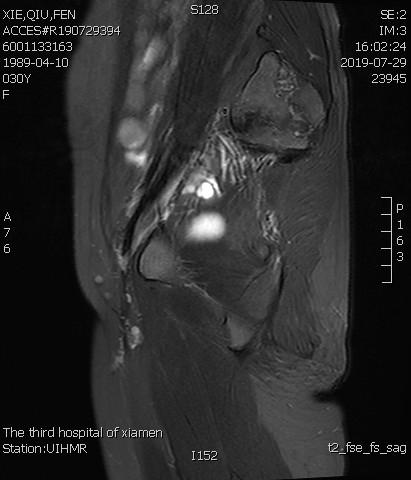

例1

青年女性患者,痛经近10年,近5年痛经明显加重。确诊为子宫腺肌症(弥漫型),经放置曼月乐、注射亮丙瑞林等妇科保守治疗,症状缓解不理想,痛经进行性加重,严重困扰工作与生活。

- 术前MRI显示子宫明显增大,病灶主要位于子宫前壁。

- 术后3个月复查MRI显示子宫明显缩小,前壁病灶萎缩坏死。